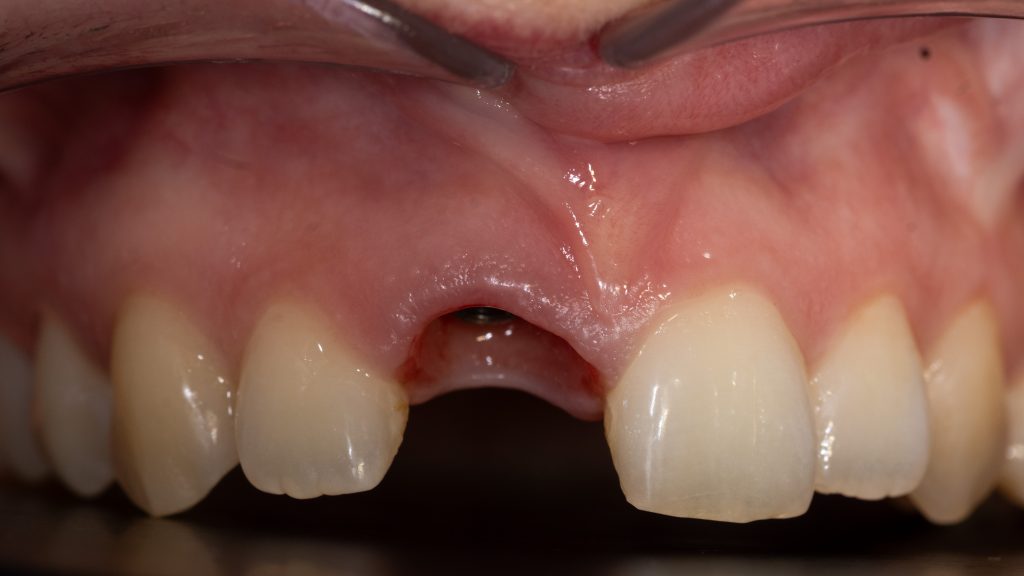

after initial healing